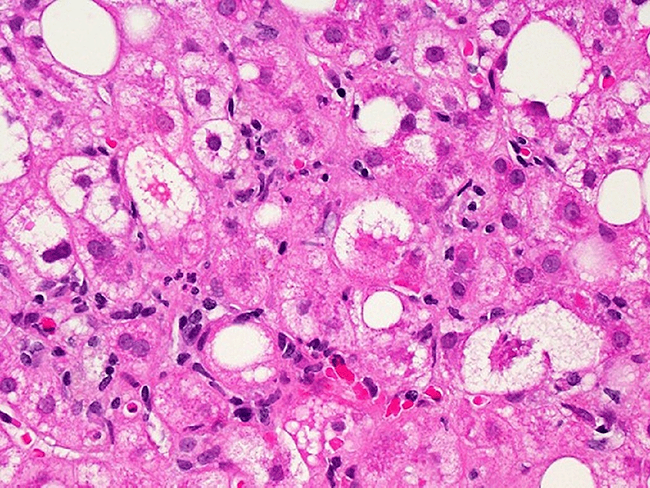

Beta cells

Endocrine/metabolic

Fractyl Health’s RJVA-001 cleared to enter clinic in Netherlands

Fractyl Health Inc. has received clinical trial application authorization in the Netherlands to initiate a first-in-human phase I/II study of RJVA-001, the first clinical candidate from the company’s Rejuva Smart GLP-1 gene therapy platform.